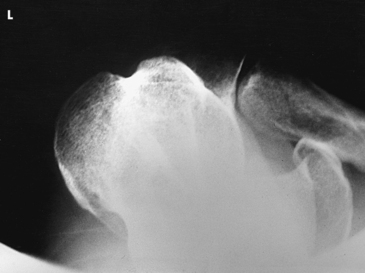

• Assist the patient in rotating the arm to avoid overstressing the shoulder joint.

Structures shown: An inferosuperior axial image shows the proximal humerus, the scapulohumeral joint, the lateral portion of the coracoid process, and the AC articulation. The insertion site of the subscapular tendon on the lesser tubercle of the humerus and the point of insertion of the teres minor tendon on the greater tubercle of the humerus are also shown. A Hill-Sachs compression fracture on the posterolateral humeral head may be seen using the Rafert modification (Figs. 5-29 and 5-30).

Fig. 5-29 A, Inferosuperior axial shoulder joint: Lawrence method. B, Inferosuperior axial shoulder joint: Rafert modification showing Hill-Sachs defect (arrow). C, Coronal MRI of shoulder joint showing Hill-Sachs defect (arrow) after recurring shoulder dislocation. (A and B, From Rafert JA et al: Axillary shoulder with exaggerated rotation: the Hill-Sachs defect, Radiol Technol 62:18, 1990. C, From Jackson SA, Thomas RM: Cross-sectional imaging made easy, New York, 2004, Churchill Livingstone.)

The West Point1 method is used when chronic instability of the shoulder is suspected and to show bony abnormalities of the anterior inferior glenoid rim. Associated Hill-Sachs defect of the posterior lateral aspect of the humeral head is also shown.

Structures shown: The resulting image shows bony abnormalities of the anterior inferior rim of the glenoid and Hill-Sachs defects of the posterolateral humeral head in patients with chronic instability of the shoulder (Fig. 5-33).